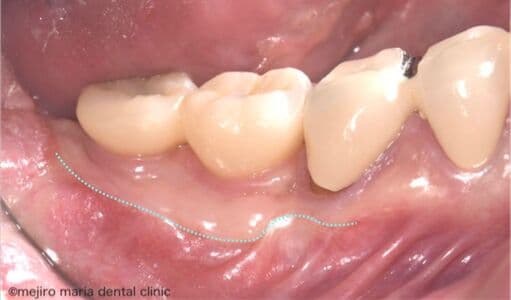

インプラントを守るための歯茎の移植(FGG)

インプラント周囲の歯茎が薄く、付着歯肉が不足していると、ブラッシング時に歯茎が動いて汚れが残りやすくなり、インプラント周囲炎のリスクが高まります。本症例では、遊離歯肉移植術(FGG)を行い、硬く安定した付着歯肉を再建しました。強い歯茎を得ることで、清掃性を高め、長期的にインプラントを健康に保つことを目指した症例です。

before

after

治療内容 遊離歯肉移植術(FGG)

治療期間 3ヶ月(移植した歯茎が落ち着くまで)

治療回数 1回(他、抜糸や経過観察を除く)

治療費用 137,500円(税込)

症例から言えること

インプラントを長く維持するためには、人工歯そのものよりも、周囲の歯肉環境が重要です。FGGにより付着歯肉を十分に確保することで、外的刺激に強く、清掃性に優れた環境を整えることができます。インプラント周囲の歯茎が薄い、磨きにくいと感じる方には、歯周形成外科的アプローチが有効な治療となります。